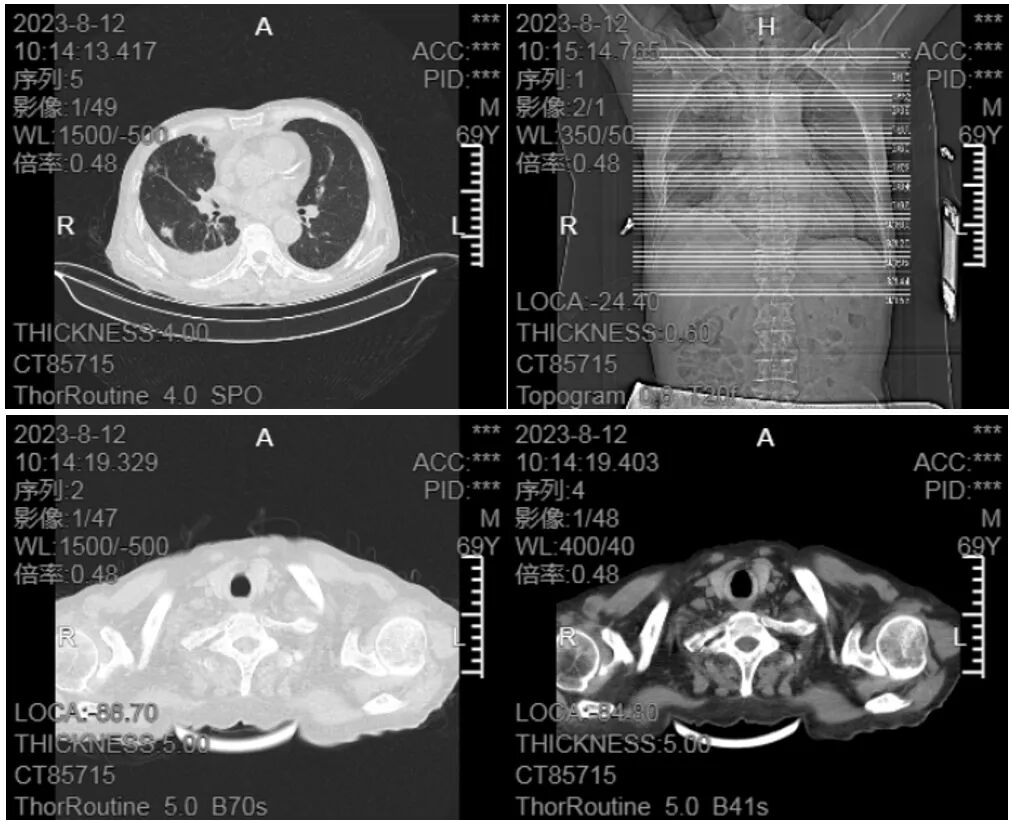

8月12日胸部CT检查提示:1.右肺多发病变,右侧胸膜增厚,右侧胸腔积液,局部包裹;2.冠状动脉钙化(图 4)。

▲图4 胸部CT检查